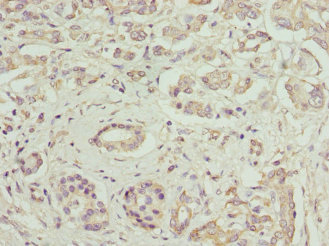

图片:

产品描述:FCGRT polyclonal antibody CSB-PA008545EA01HU was produced in the rabbits immunized by using the Recombinant Human IgG receptor FcRn large subunit p51 protein (24-297AA) as the immunogen. The target protein FCGRT is a cell surface receptor that binds the Fc region of monomeric immunoglobulin G. This protein transfers immunoglobulin G antibodies from mother to the newborn across the placenta. Besides, it also binds immunoglobulin G to protect the antibody from degradation. Diseases associated with FCGRT include selective Igg deficiency disease and immunodeficiency.

This Rabbit anti-Homo sapiens (Human) FCGRT Polyclonal antibody was tested in the ELISA, WB, IHC and IF applications. The non-conjugated IgG got purified by protein G and reached up to 95% in purity. It reacts with the FCGRT proteins of human or mouse-origin and may be used to detect the endogenous levels of FCGRT protein. -

应用范围:ELISA, WB, IHC, IF

Application Recommended Dilution WB 1:500-1:2000 IHC 1:20-1:1000 IF 1:50-1:200 -